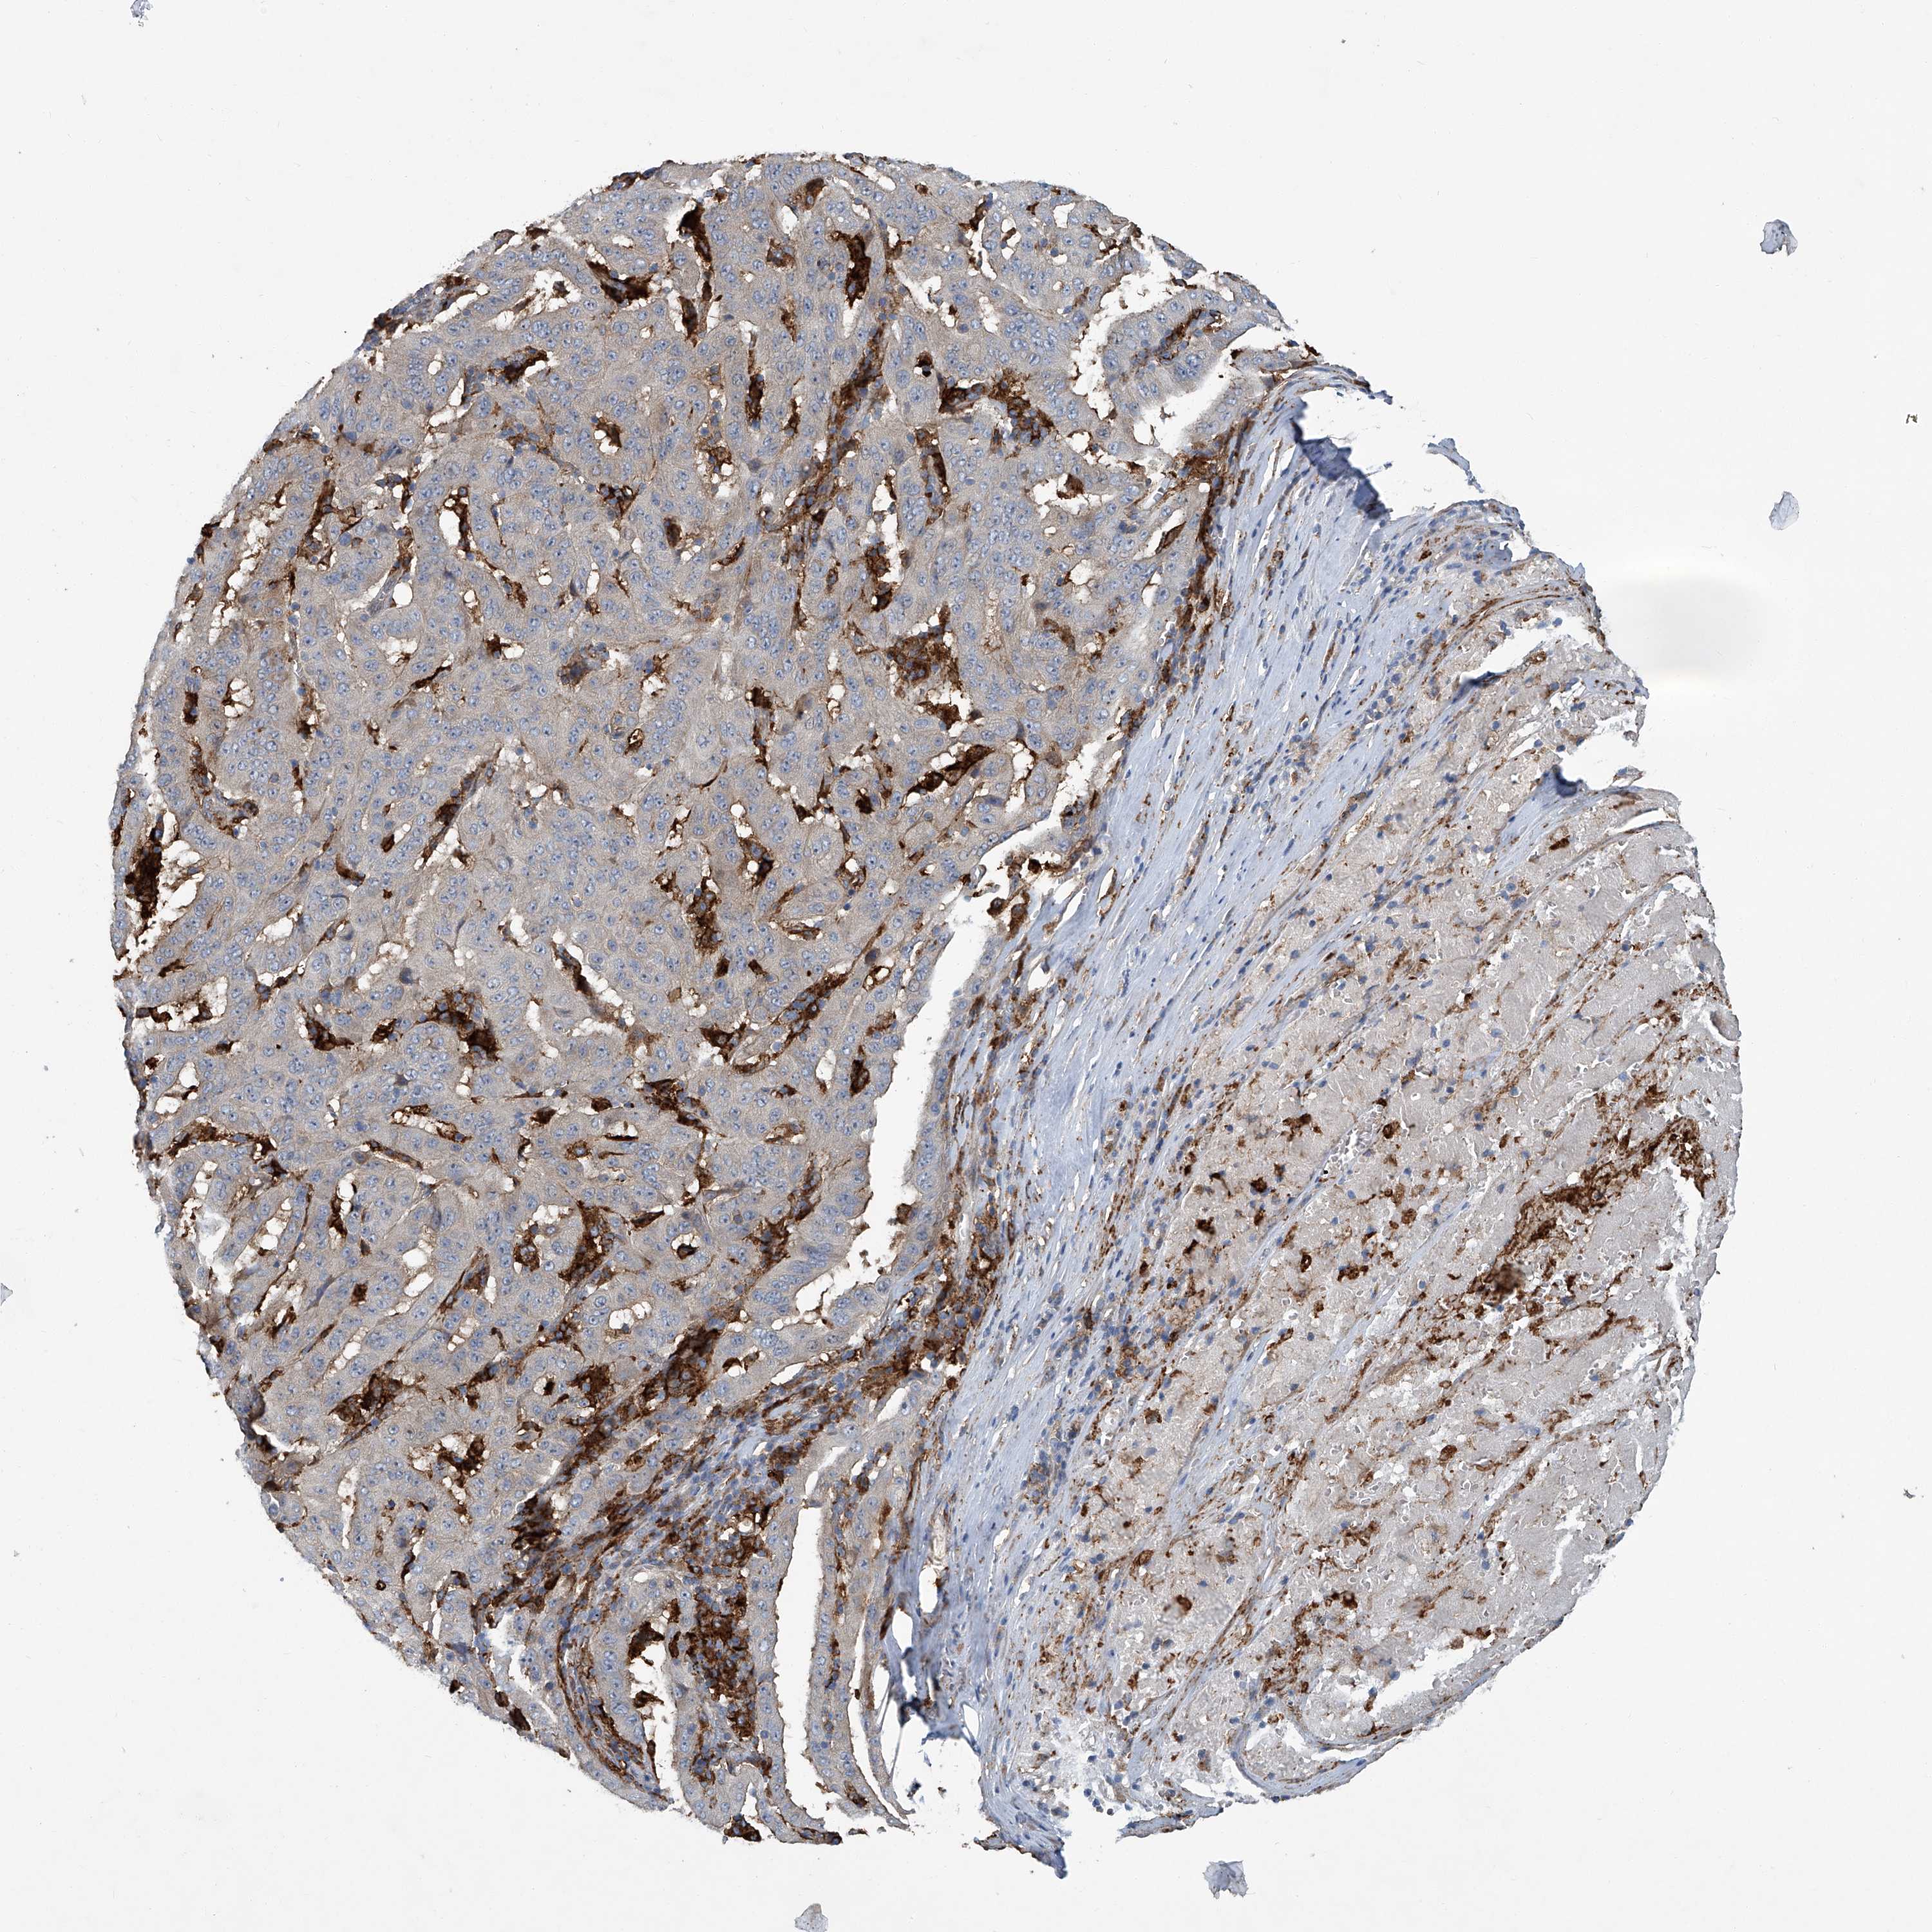

PANCREATIC CANCER - Protein expressioni

A mouse-over function shows sample information and annotation data. Click on an image to view it in a full screen mode. Samples can be filtered based on level of antibody staining by selecting one or several of the following categories: high, medium, low and not detected. The assay and annotation is described here.

Note that samples used for immunohistochemistry by the Human Protein Atlas do not correspond to samples in the TCGA dataset.

Antibody stainingi

Antibody staining in the annotated cell types in the current human tissue is reported as not detected, low, medium, or high, based on conventional immunohistochemistry profiling in selected tissues. This score is based on the combination of the staining intensity and fraction of stained cells.

Each image is clickable and will lead to virtual microscopy that enables deeper exploration of all samples and also displays staining intensity scores, fraction scores and subcellular localization as well as patient and tissue information for each sample.

Antibody HPA023915

Antibody HPA030426

Staining

High

Medium

Low

Not detected

Intensity

Strong

Moderate

Weak

Negative

Quantity

>75%

75%-25%

<25%

None

Location

Nuclear

Cytoplasmic/membranous

Cytoplasmic/membranous,nuclear

Adenocarcinoma, NOS